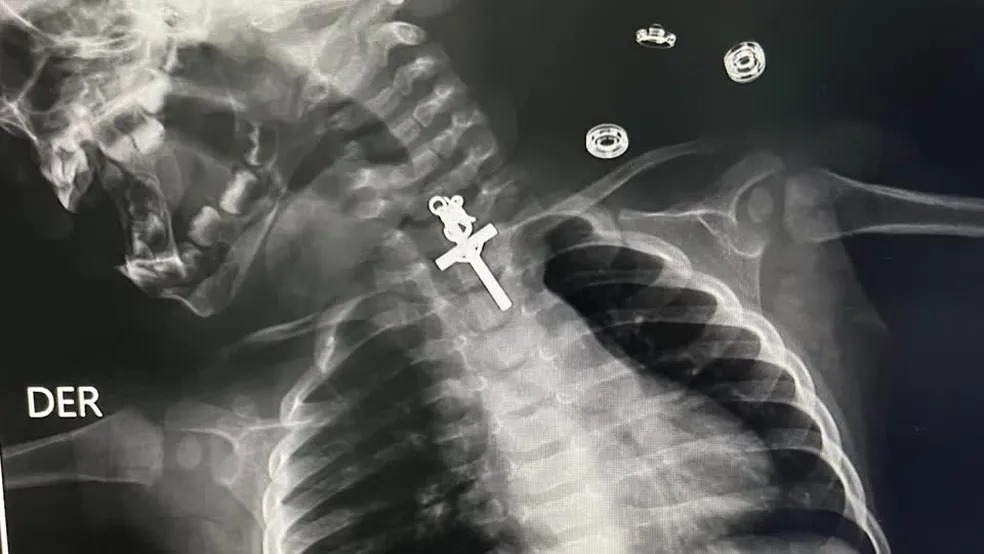

Um bebê, de apenas 10 meses, ficou com um crucifixo preso na garganta depois de tentar engolir o objeto. A criança precisou passar por uma endoscopia para a retirada do objeto, no sábado (11), no Peru.

Após a realização de exames, os profissionais de saúde perceberam que o bebê havia engolido um crucifixo. O médico Luis Esteves Cabanillas disse que o procedimento para a retirada do objeto foi complicado.

"Mesmo quando tentamos retirá-lo inicialmente, não conseguimos, estava preso, então tentamos várias vezes", afirmou.